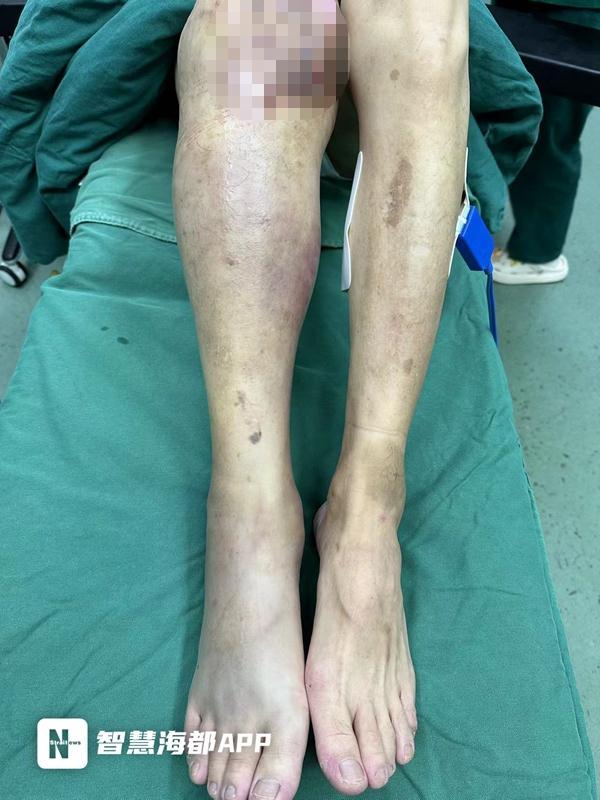

患者右腿明顯腫脹

“人送來時,高燒39.5℃,精神萎靡,血壓低,出現膿毒性休克、多臟器功能不全;從右足背到右大腿腫脹明顯,皮膚發烏,局部出現血皰,肢體冰涼,右下肢廣泛缺血性壞死。”接診的燒傷創面修復科主治醫師魏智藝立即給予補液抗休克、抗感染、臟器功能維護等一系列治療,并對右下肢進行搶救性手術。